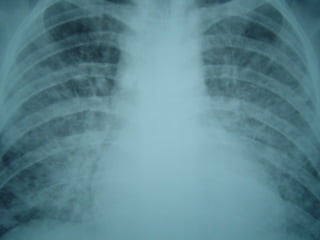

Histoplasmose Disseminada e

Pulmão

• Rx: infiltrados em bases pulmonares + adenomegalia

• RX: envolvimento simétrico, ápices, cavitações

Rx de Tórax 74% alterado